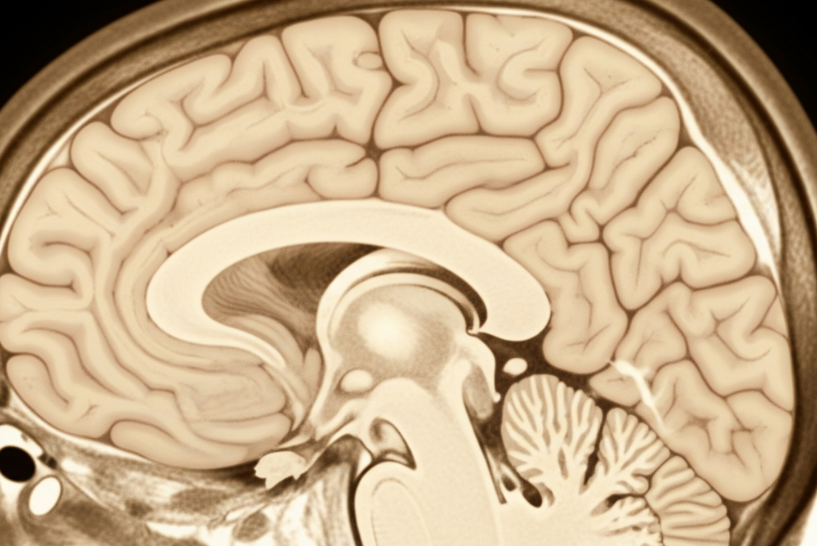

- 뇌 영상 검사: CT, MRI 등을 통해 뇌 위축 정도나 혈관성 병변 등을 확인하여 치매의 원인을 감별합니다.